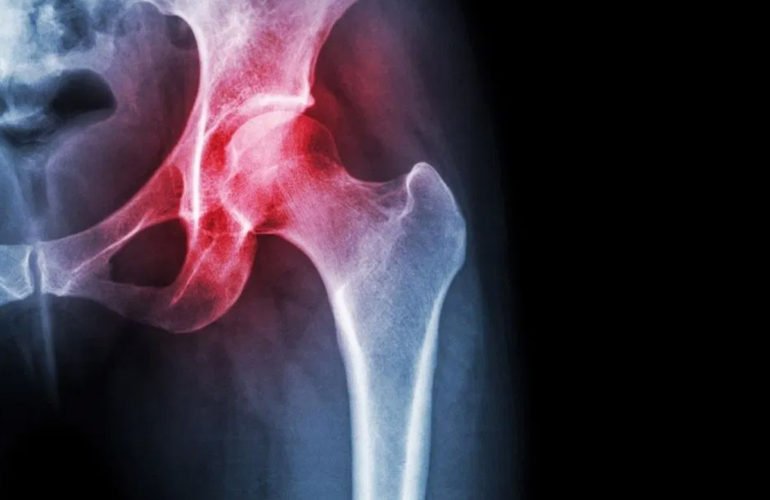

A figura 1 mostra uma radiografia de um paciente com necrose asséptica da cabeça femoral bilateral. O lado direito esta em um estagio mais avançado, enquanto o lado esquerdo as alterações radiográficas são quase imperceptíveis.

A Radiografia (Rx) é extremamente importante e útil para o acompanhamento desta patologia. Apesar de nas fases bem iniciais ser normal , logo já surgem alterações visíveis. Este é o melhor método para acompanhar a progressão da doença.